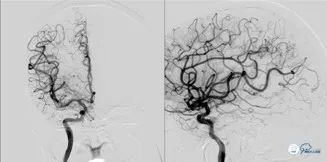

入院急查全脑血管造影术:可见基底动脉高密度征。

可见基底动脉尖端部血栓,呈次全闭塞态势,前向血流Mtici 2*级A**,无明显前循环向后循环代偿。